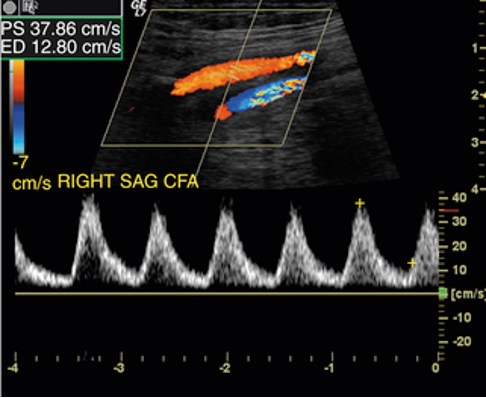

indirect sono findings:

monophasic CFA spectral tracings (normal CFA tracings are triphasic)

PSV </= 45cm/s

may-thurner syndrome

aka iliac vein compression syndroms (IVCS)

lt. common iliac vein is compressed bw the rt. common iliac artery and the underlying vertebral body

pts. usually present w left iliofemoral DVT or chronic left lower extremity pain & edema

may see loss of phasicity in lower venous sys

While scanning a patients' left lower leg, you notice the common femoral vein flow is continuous without any respiratory variation. What do you suspect this patient may have?